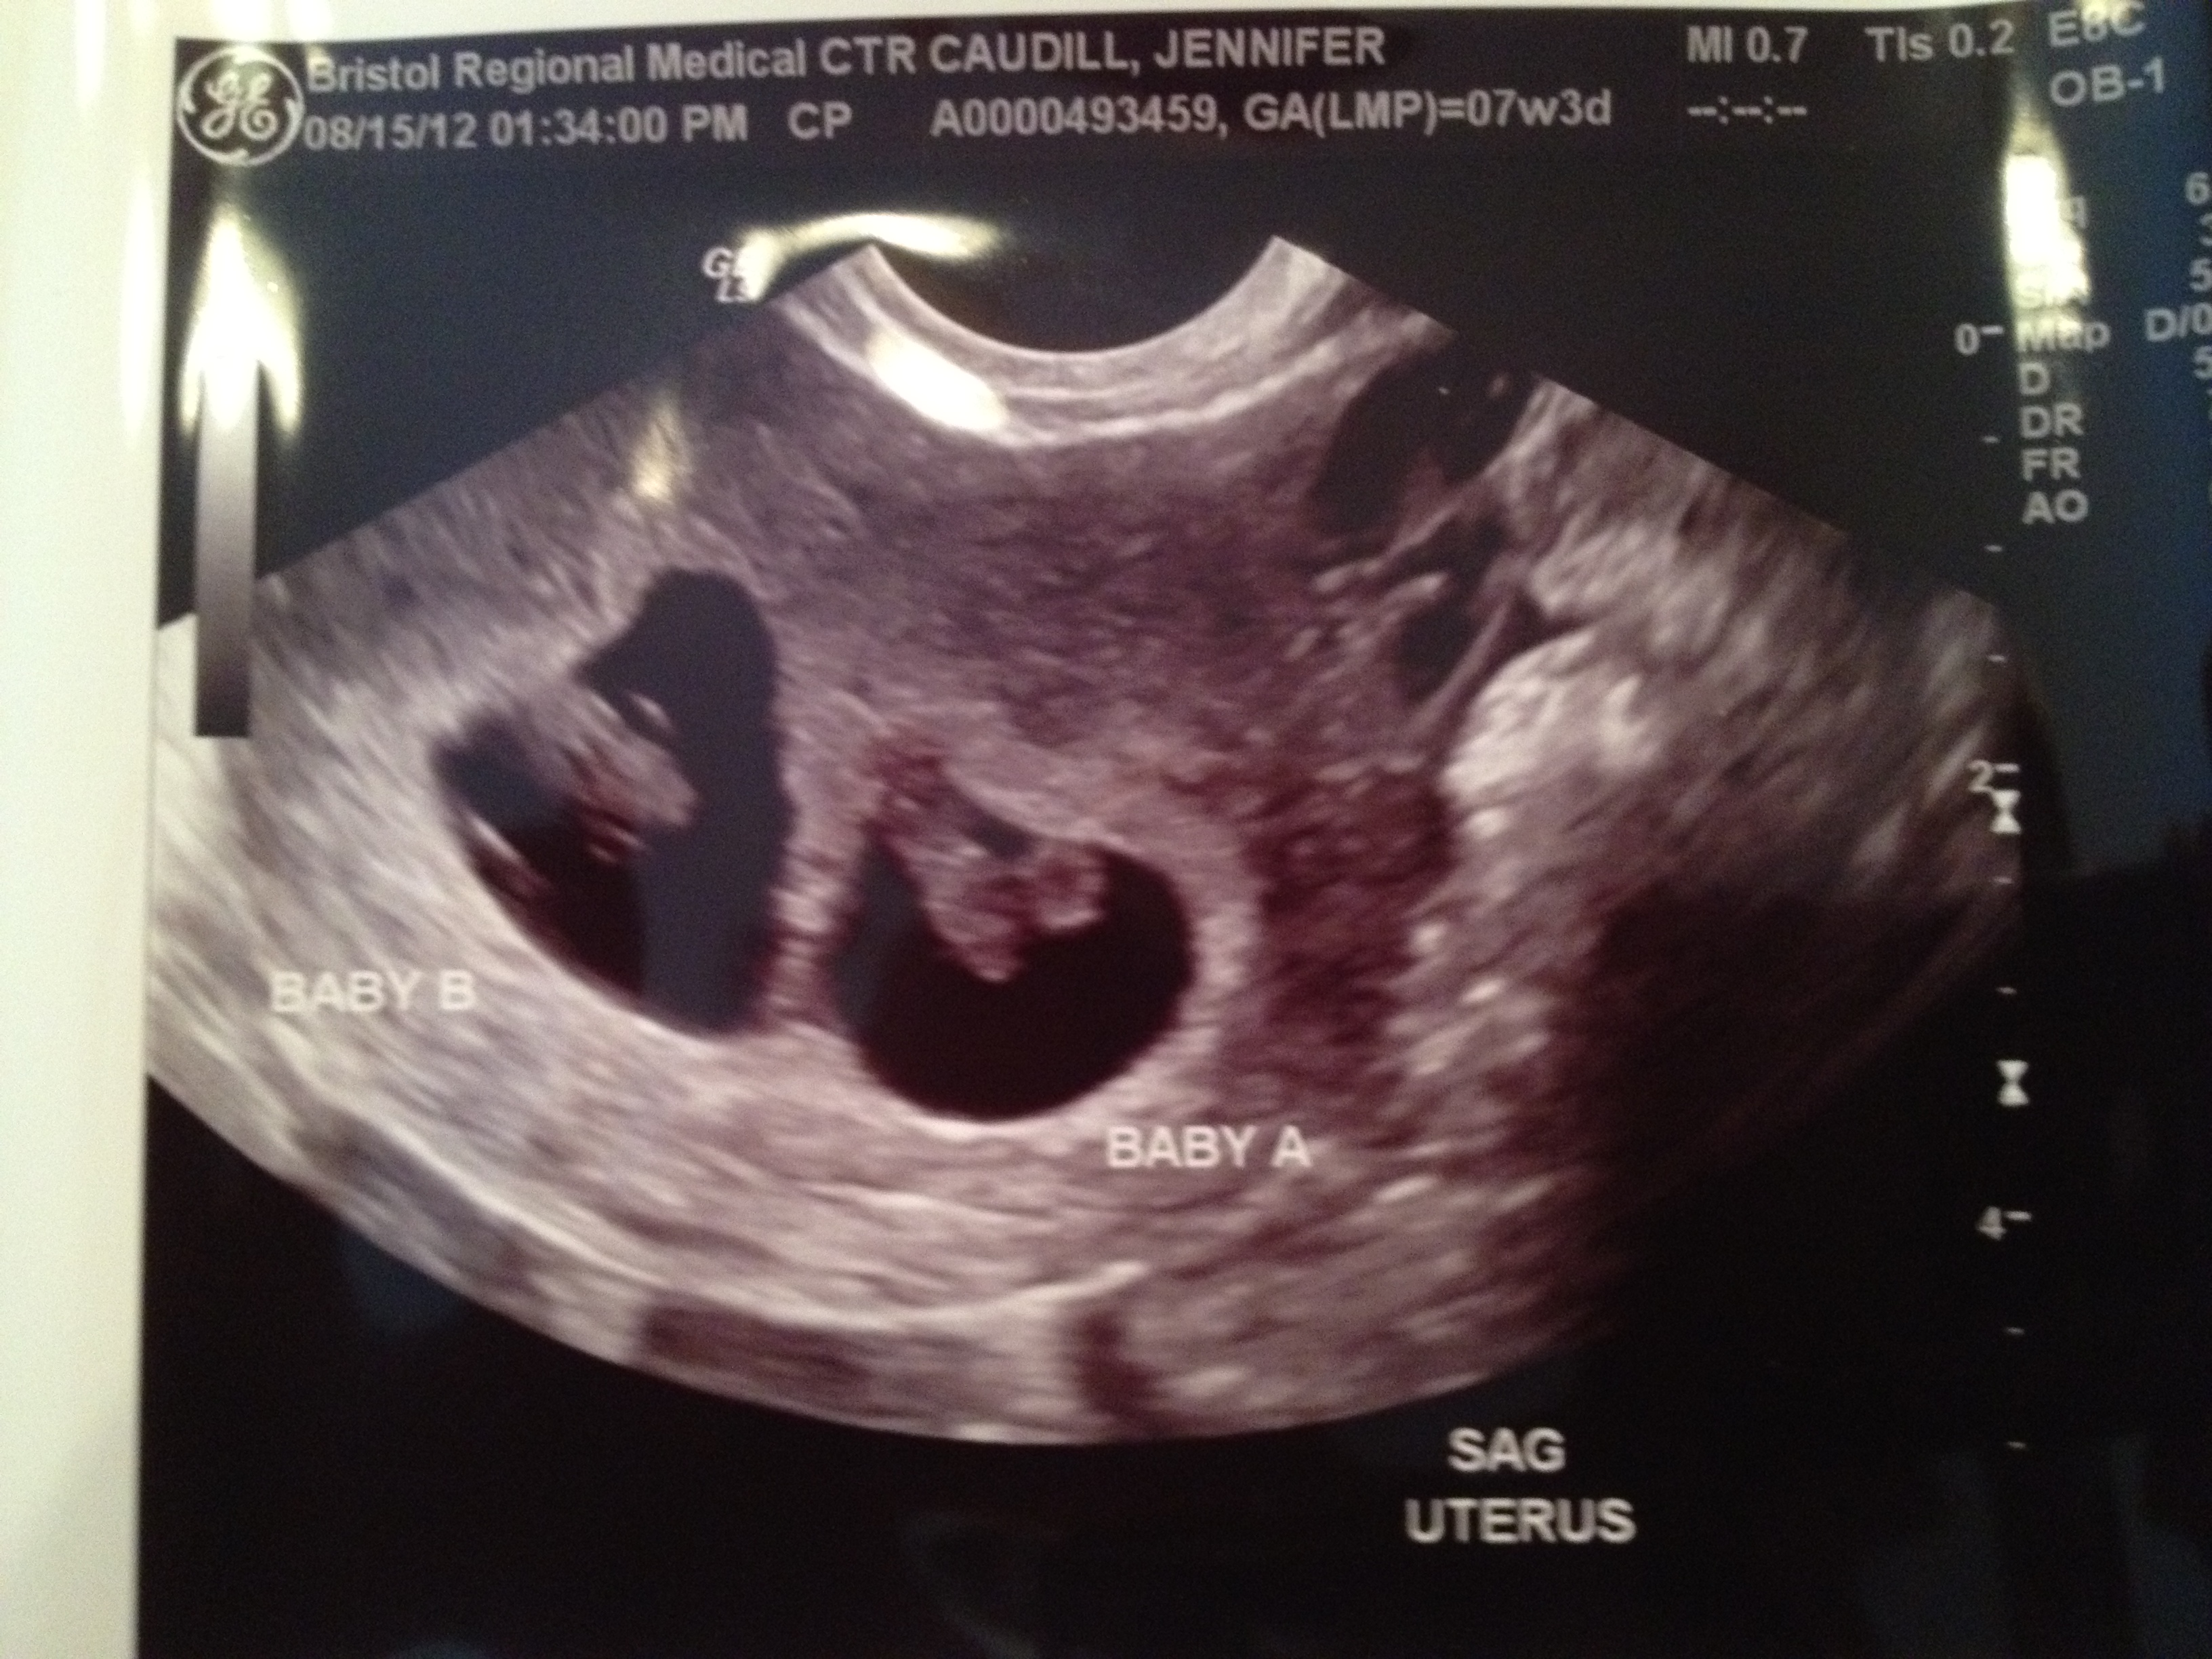

When we found out we were having twins, we were almost instantly also told that twins almost always come early and that 37 weeks is considered “term” for twins. That being said, my doctor’s goal was to make it to 38 weeks (he was a very optimistic guy). As the pregnancy went on and I read more about twins and their moms, our goal was to make it to 36 weeks, but we were prepared for as early as maybe 34 weeks. Given that my due date was April 3 if I were to carry them the full 40 weeks, that meant that our babies could be born anywhere from about mid-February to about mid-March. In my gut, I always knew they’d be earlier than expected or planned, but never in my wildest dreams was I prepared for January babies.